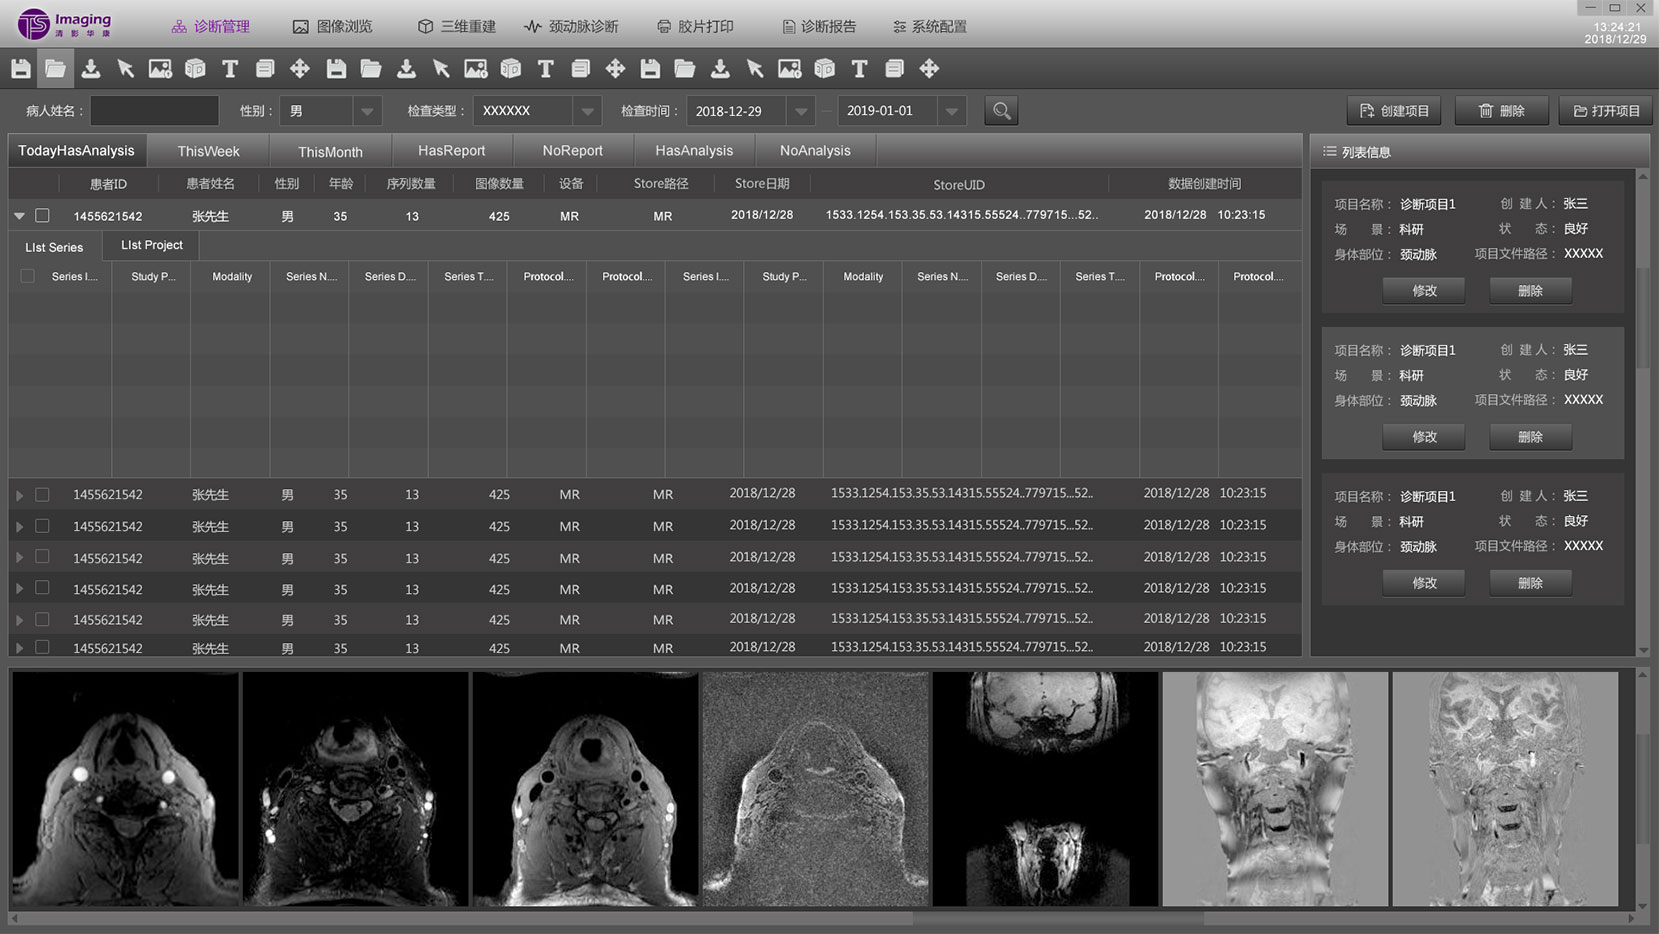

診斷管理頁面

診斷管理頁面相對其他頁來說交互關系比較復雜,表單里面還套了一個子表,為了更好的區分兩者,tab的形式、底色和字體大小等等做了明顯的區分。這部份也是在設計過程中調的較多的地方。左側是一個信息列表的展示,通過下方的按鈕也可進行操作。下方是影像的縮略圖,點擊之后可放大。